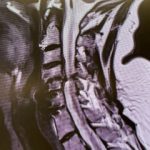

Current imaging studies (Figs. 1 and 2) demonstrated significant degenerative collapse of C45 segment, retrolisthesis and with severe right foraminal stenosis as well as C3-4 degenerative disc degeneration with moderate compression of thecal sac. Patient failed conservative management and it was decided, given her prior two anterior procedures, that an excellent decompression could be accomplished with a posterior laminectomy, foraminotomy and fusion to maintain alignment.

(Fig. 2) Axial T2 cervical MRI at C4-5 demonstrating significant osteophytic disease with bilateral neural foraminal compression of the C5 nerve roots, right greater than left.